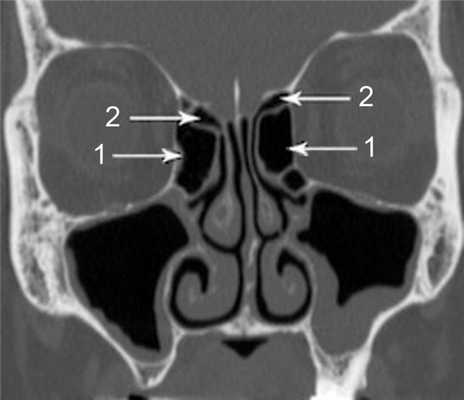

(Слева) На аксиальной КЛКТ справа и слева визуализируются добавочные устья ниже уровня соответствующих крючковидных отростков. Основные устья находятся на другом уровне и не видны на этом срезе.

(Справа) На корональной КЛКТ у этого же пациента визуализируются дополнительные устья справа и слева. Основные устья на этом срезе не видны. Обратите внимание на субтотальное снижение пневматизаци левой верхнечелюстной пазухи.